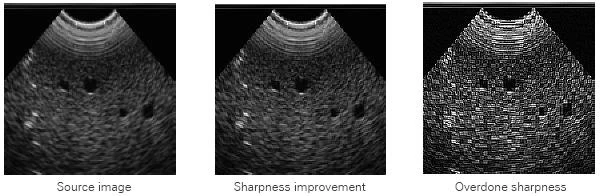

You may use this mechanism to enhance blurred images. Overdoing its application leads, however, to distortions: